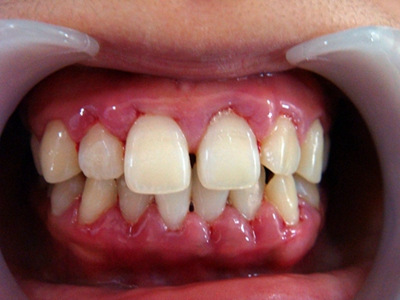

牙龈炎是发生于牙龈组织的炎症,患者可出现牙龈出血伴肿胀、发红、正常形态改变和偶尔不适等症状。本病主要由口腔卫生状况差导致,包括口腔不洁、牙菌斑等,诊断依据临床检查,治疗包括专业牙齿清洁和加强家庭口腔卫生。

牙龈炎可先引起牙齿与牙龈之间的沟(龈沟)加深,然后牙龈充血,炎症围绕一个或多个牙齿,伴牙龈乳头肿胀和易出血。一般无痛,可自行消退,也可维持轻度炎症数年。